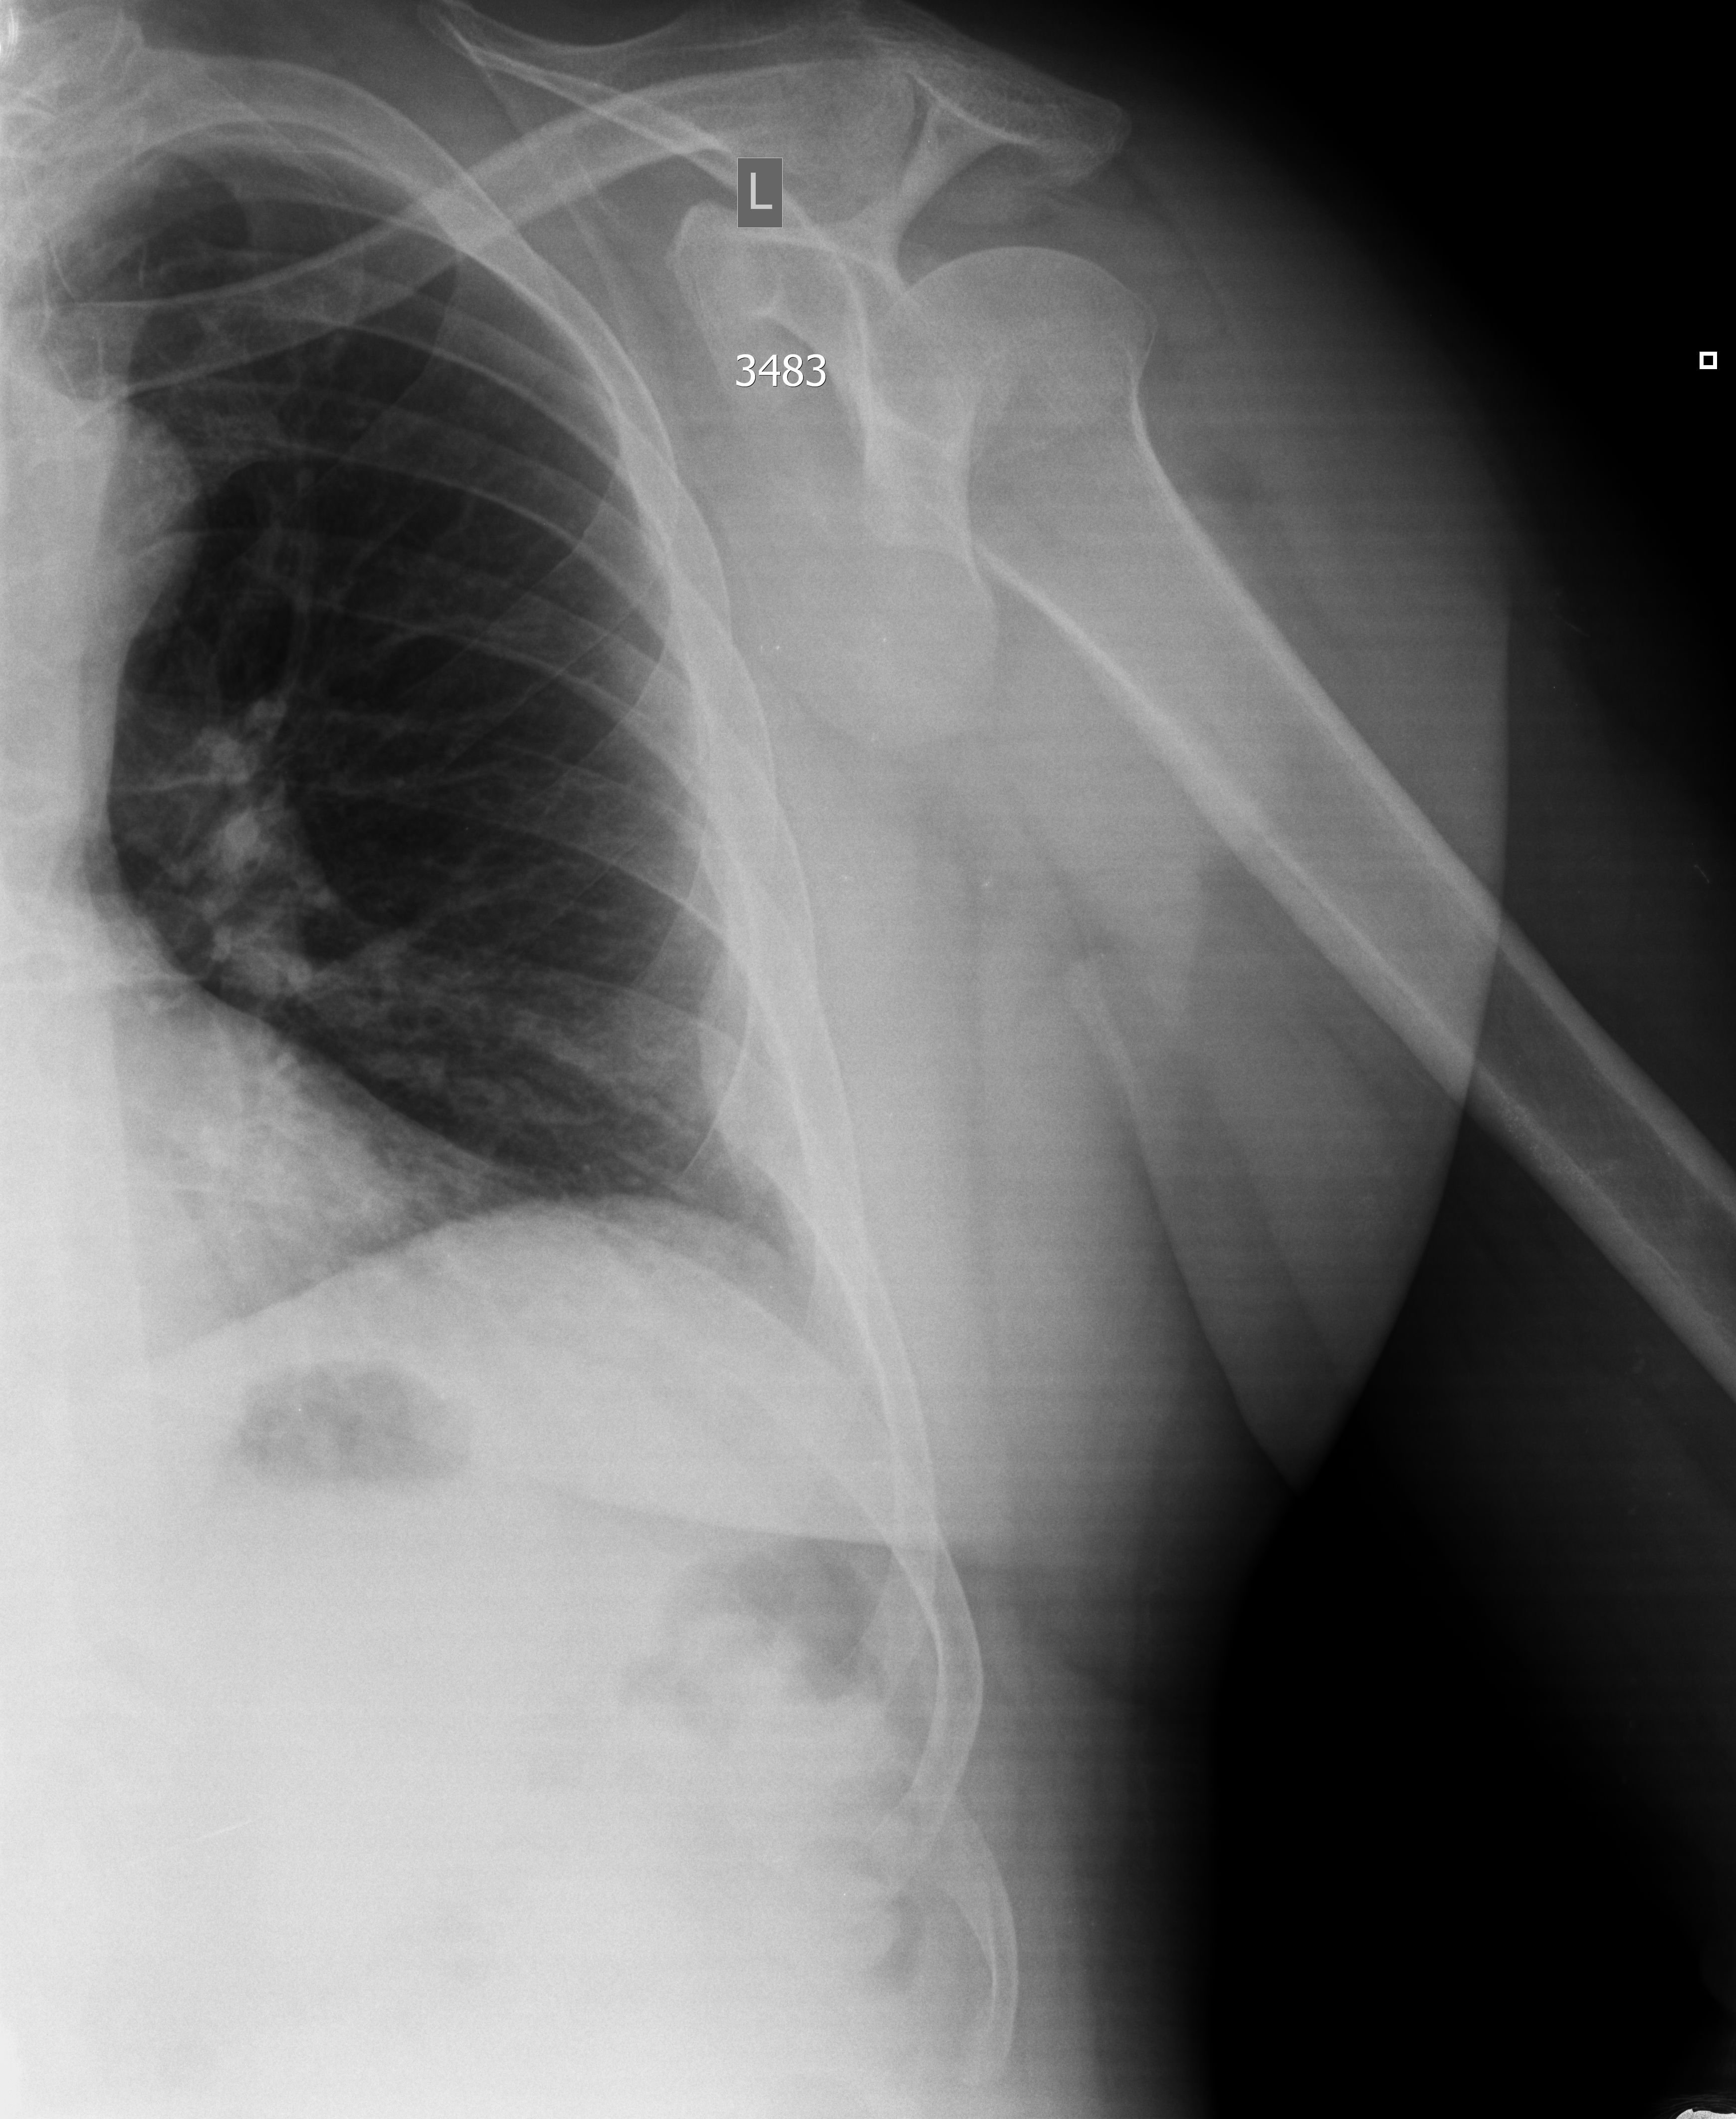

Мужчина, 59 лет, перелом ребра, травма месяц назад. Формирование костной мозоли.

Рентген - ответ отрицательный.